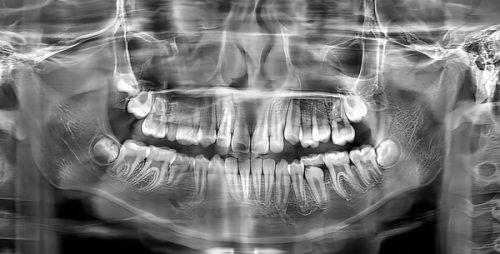

科室设置与服务项目

全好口腔门诊部开设了多个科室,涵盖种植科、正畸科、美学修复科、综合诊疗、儿童牙科等。种植科可以为缺牙患者提供专精的牙齿种植服务,无论是单颗牙缺失还是多颗牙缺失,甚至全口/半口牙齿缺失,都能在这里找到合适的解决方案。正畸科则针对牙齿不整齐、咬合问题等提供矫正服务,帮助患者拥有整齐美观的牙齿和健康的咬合关系。美学修复科注重牙齿的美观与功能相结合,通过各种修复手段改善牙齿的外观和色泽。综合诊疗科室可以处理常见的口腔疾病,如龋齿、牙周炎等。儿童牙科则专门为小朋友提供口腔护理和治疗服务,让孩子们从小养成良好的口腔卫生习惯。